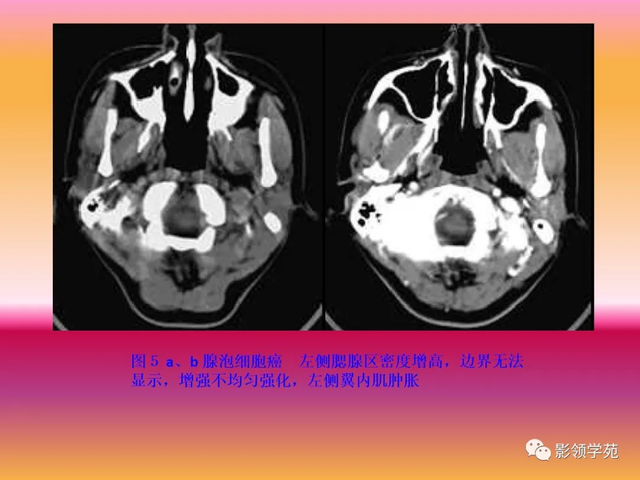

腮腺恶性肿瘤CT体现:

边缘不规则或分叶;

密度不均,可有出血、坏死、液化、囊变

与相近 结构差异水平粘连,对周围腺体呈侵蚀性体现,易向腺外结构侵占 ,使腺体与周围脂肪、肌肉组织间隙中的筋膜模糊或消逝 。

增强,不均质强化。

颈部淋投合肿大及转移征象。

面神经受侵占 的变现:

乳突尖、茎突骨质收破损 的变现;

茎乳孔与腮腺间的脂肪间隙消逝 ;

下颌后静脉受累移位。

恶性肿瘤可沿神经周围侵占 ,即肿瘤沿神经内膜、神经束膜或神经淋巴管扩散、伸张 。最常受累的为面神经及三叉神经